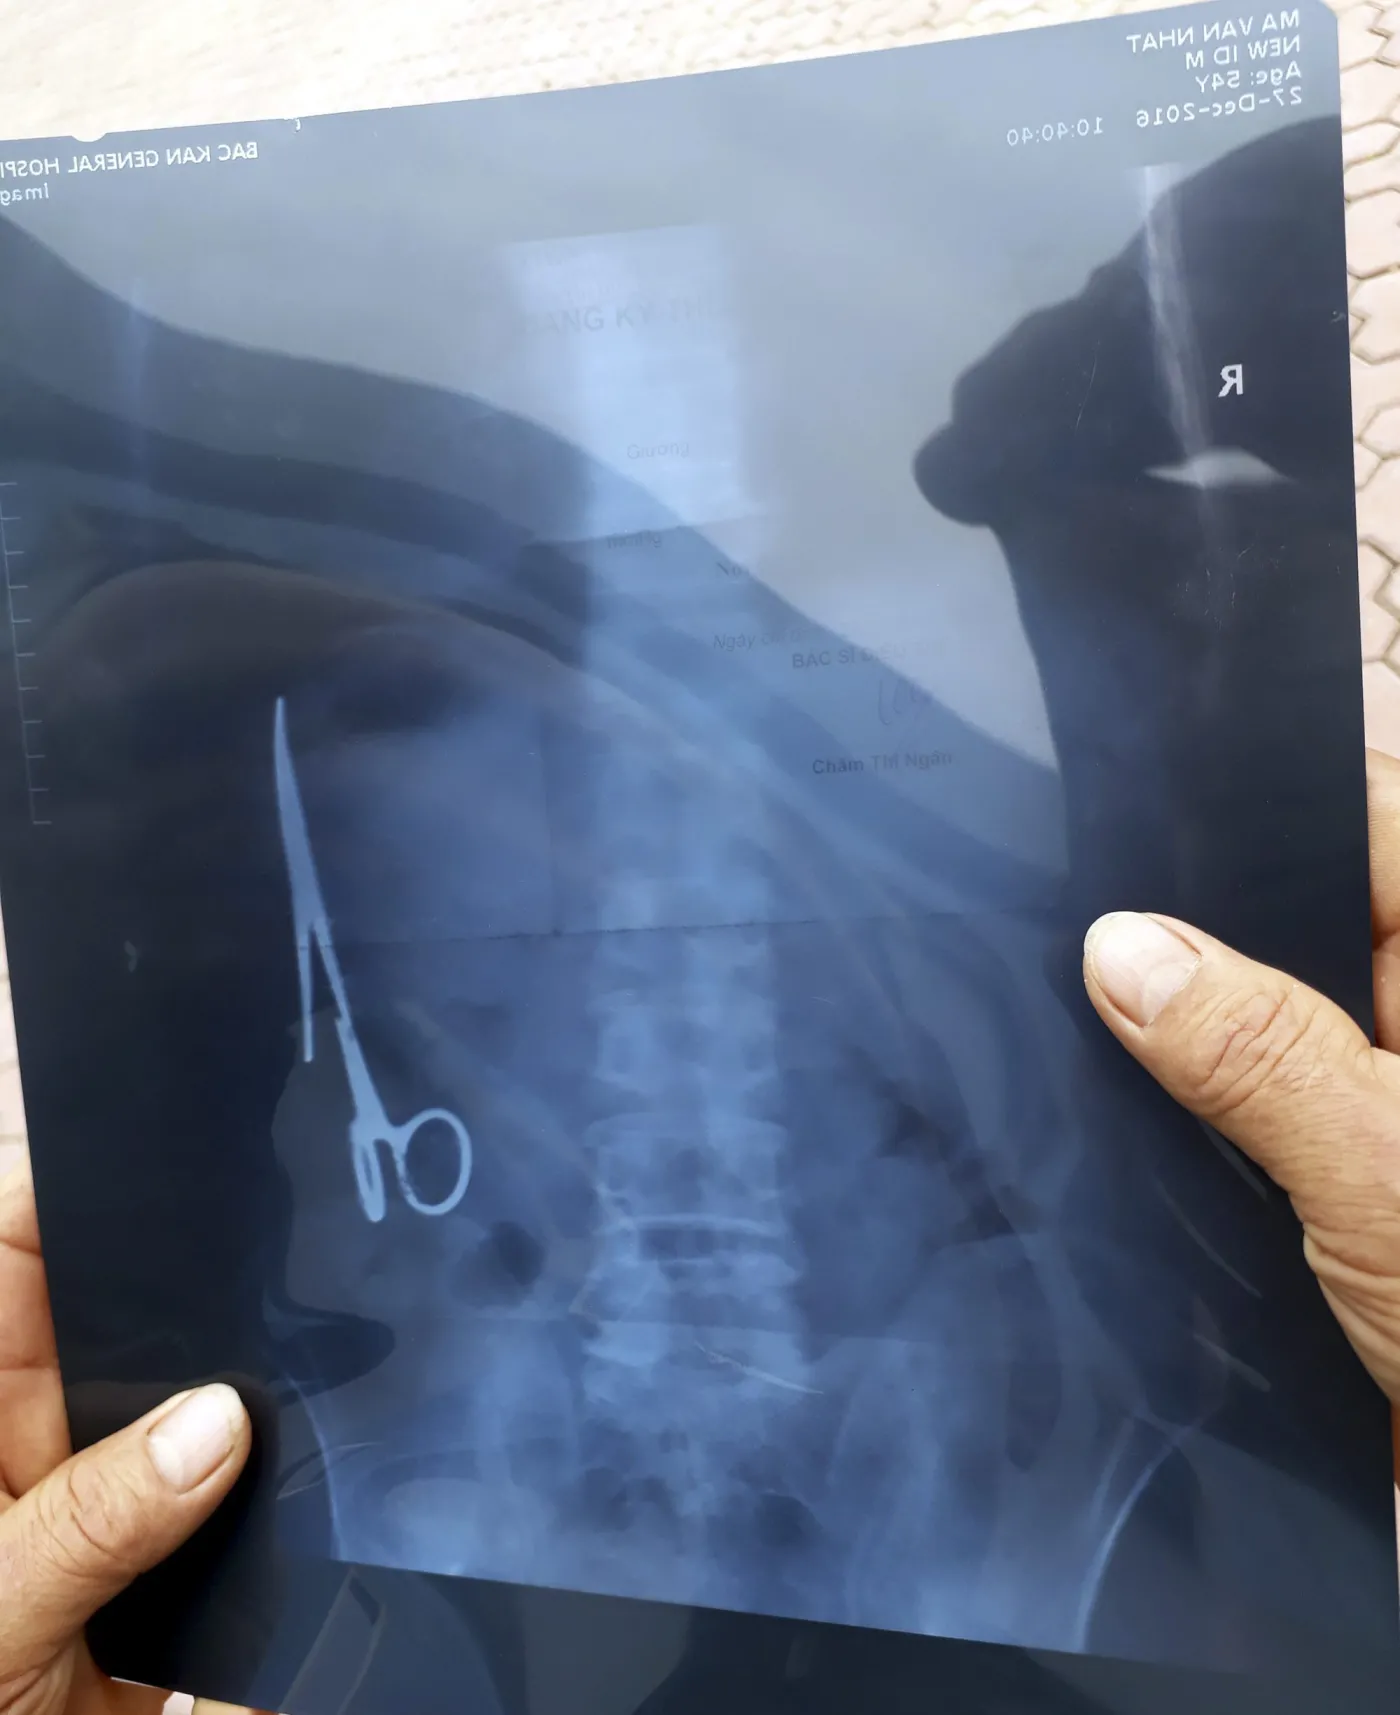

Ma Van Nhat, 54-letni mieszkaniec Wietnamu, chodził z tą zgubą w brzuchu przez 18 lat. Chirurg zaszył w nim nożyczki, kiedy Ma Van Nhat trafił na stół operacyjny po wypadku drogowym. Przez długi czas mężczyzna uskarżał się na wewnętrzne boleści, jednak przekonany był, że spowodowane są one problemami pourazowymi. Jakież było jego zdziwienie, gdy w trakcie badań lekarz radiolog wykonał prześwietlenie jego brzucha. Na fotografii rentgenowskiej dały się zauważyć 15-centymetrowe stalowe nożyczki.

Usunięcie pozostawionego narzędzia z brzucha mężczyzny zajęło lekarzom mniej więcej trzy godziny. Szef szpitalnego zespołu chirurgów zapewnił pacjenta, że liczba nożyczek i skalpeli po zakończeniu operacji zgadzała się z liczbą narzędzi sprzed operacji.